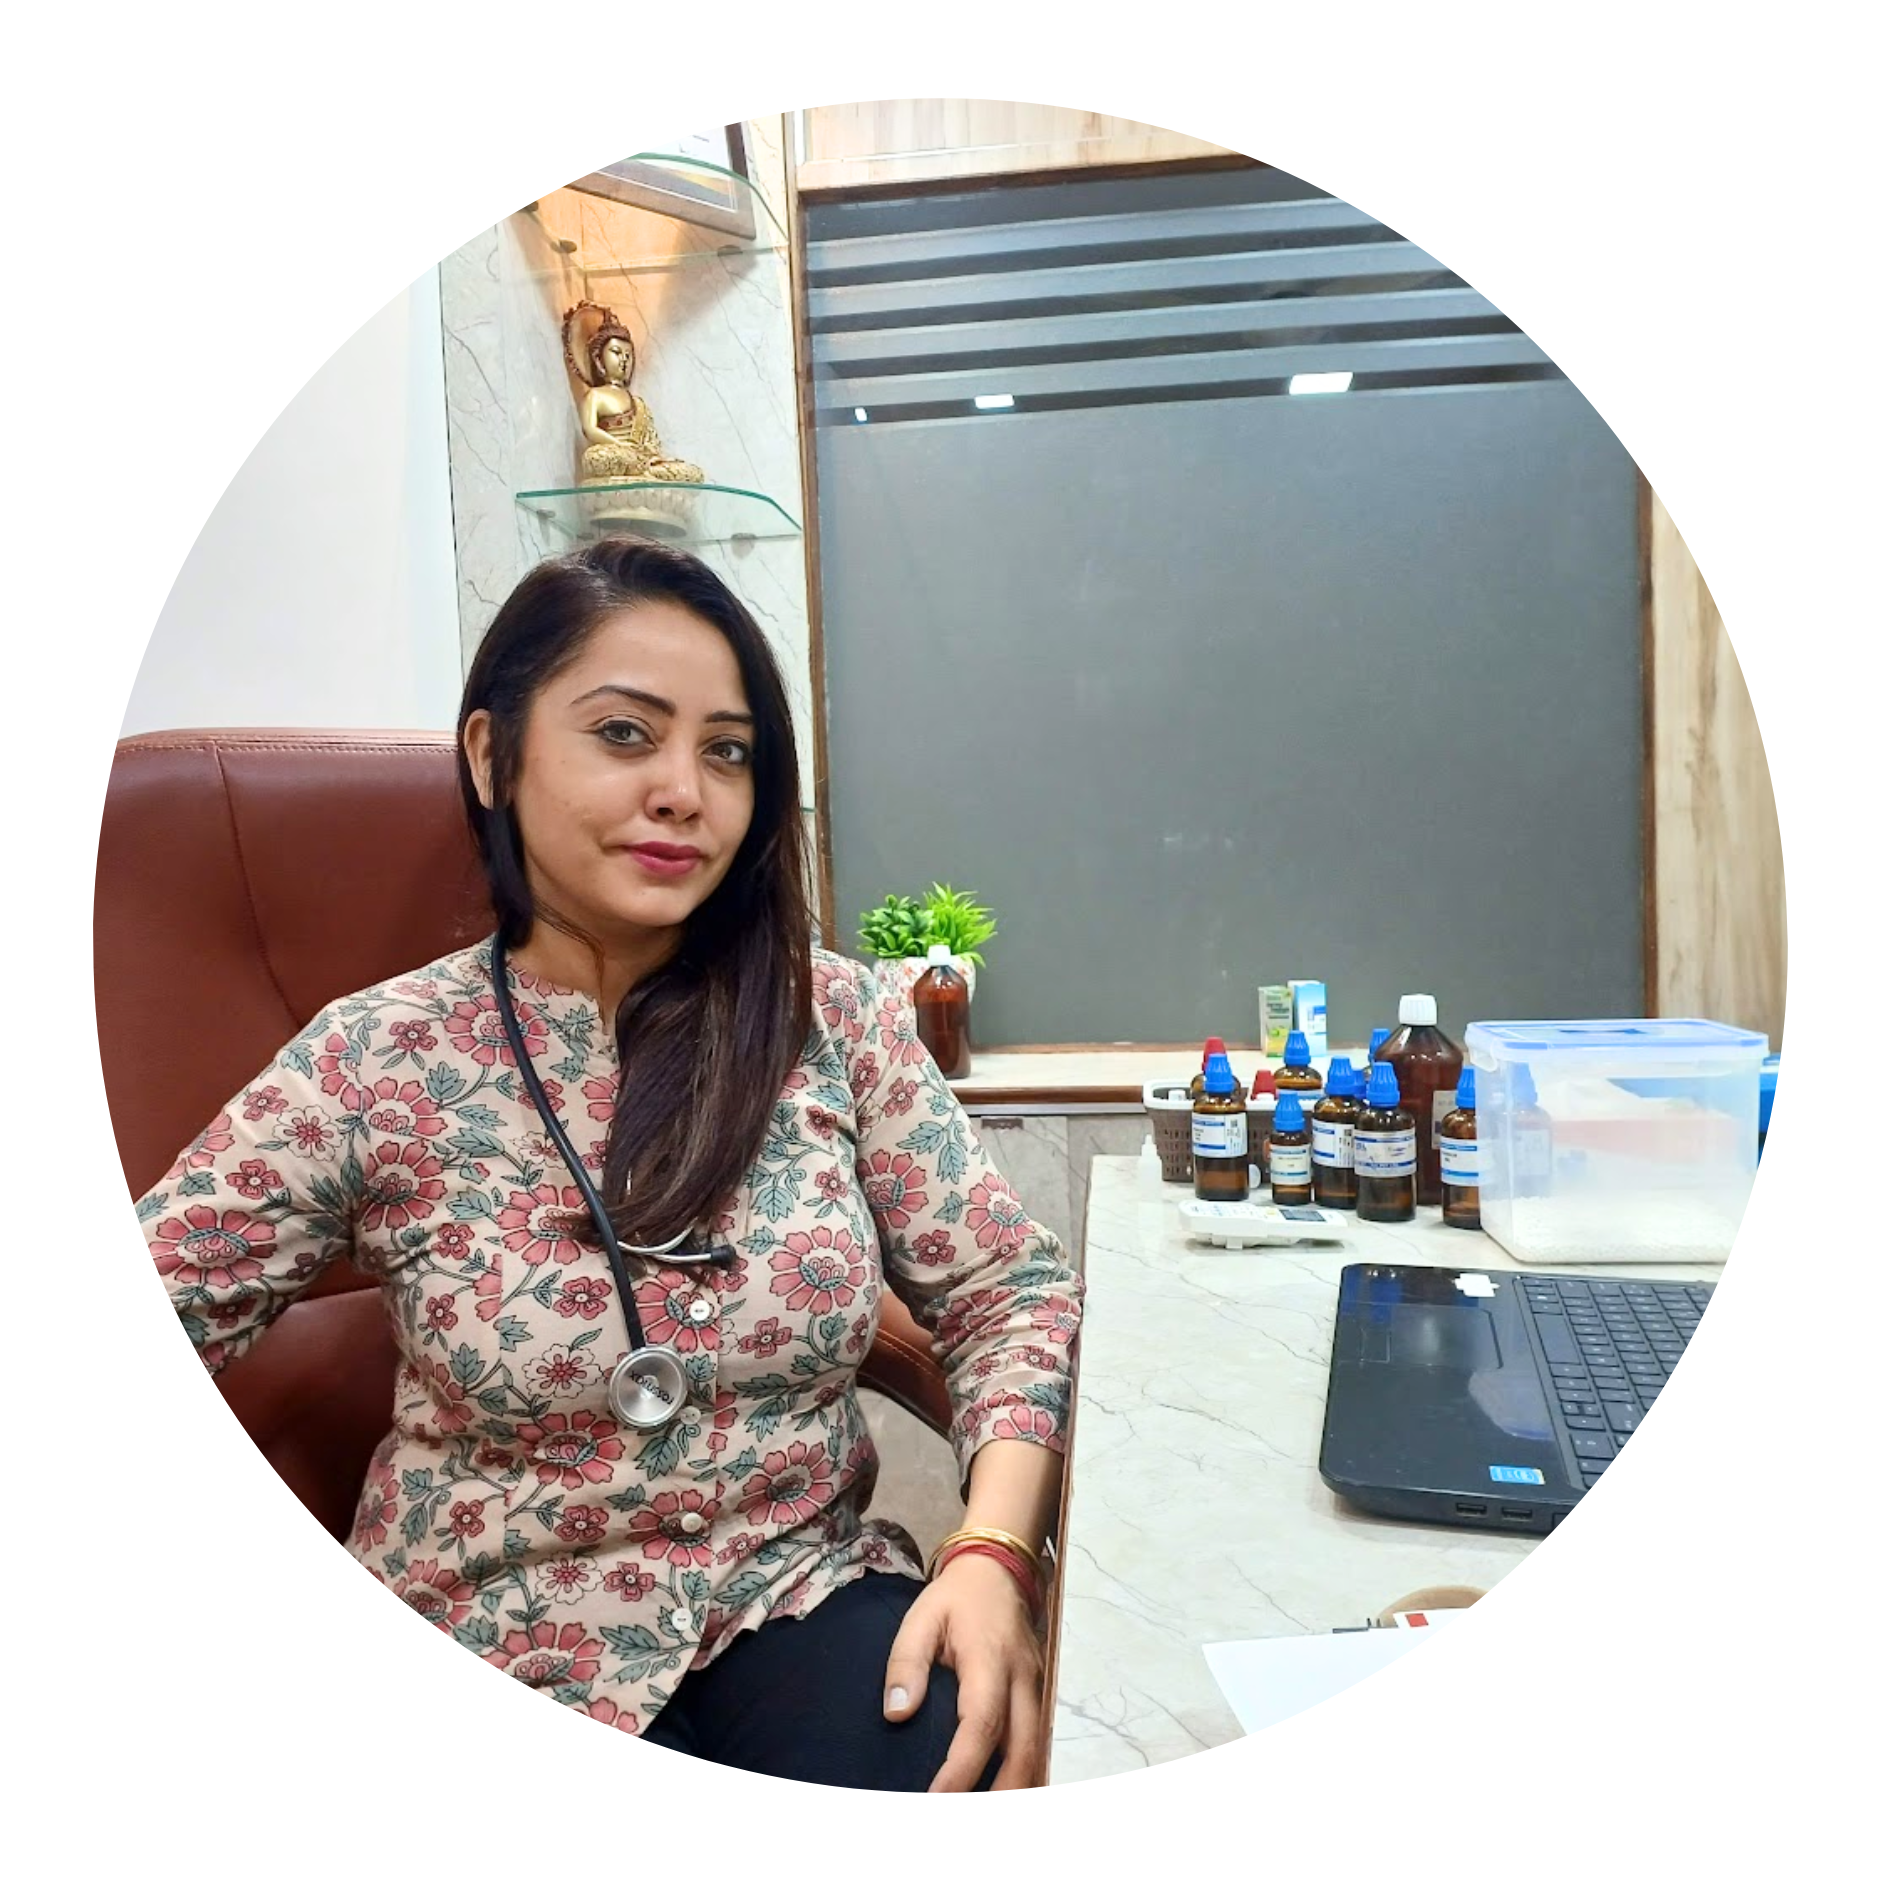

Dr. Megha Suneja, an alumni of NHMC, is a renowned Senior Homeopathic Consultant and the founder of Dr. Megha’s Advance Homoeo Clinic, which operates two branches in Delhi. With over 15 years of rich clinical experience, she specializes in the homeopathic management of complex and chronic conditions such as Cancer, Chronic Kidney Failure, Liver Failure & Cirrhosis, Infertility, and Lifestyle Disorders including Hypertension (B.P), Uncontrolled Diabetes, High Cholesterol, and Hormonal Diseases such as PCOD and Thyroid through advanced, evidence-based homeopathy. Her approach focuses on identifying and treating the root cause while restoring natural balance and wellness.

Driven by her passion to modernize homeopathy, Dr. Megha combines advanced diagnostic methods with individualized homeopathic therapeutics to deliver precise and lasting results. Her dedication, compassion, and clinical excellence have earned her the trust of thousands of patients across India and abroad.

Dr. Megha has been felicitated by the late Dr. A.K. Walia, then Health Minister of Delhi, for her outstanding community service in the Laxmi Nagar constituency in association with the Jan-Mitra NGO.

She has been awarded the prestigious Rashtriya HomyoShree Puraskar 2025 as the Best Doctor for excellence in Homoeopathic Practice by the Akhil Bhartiya Chikitsa Association (Registered under Govt. of India).

She has been a Guest Speaker at numerous homeopathic seminars across Delhi-NCR and holds a long-standing association with H.H.F, where she has served as a Core Member and respected speaker of the Delhi State Committee. She has been recognized for her work in the Management Committee and for her contributions as a Mentor, Guide, and Lecturer within the organization.